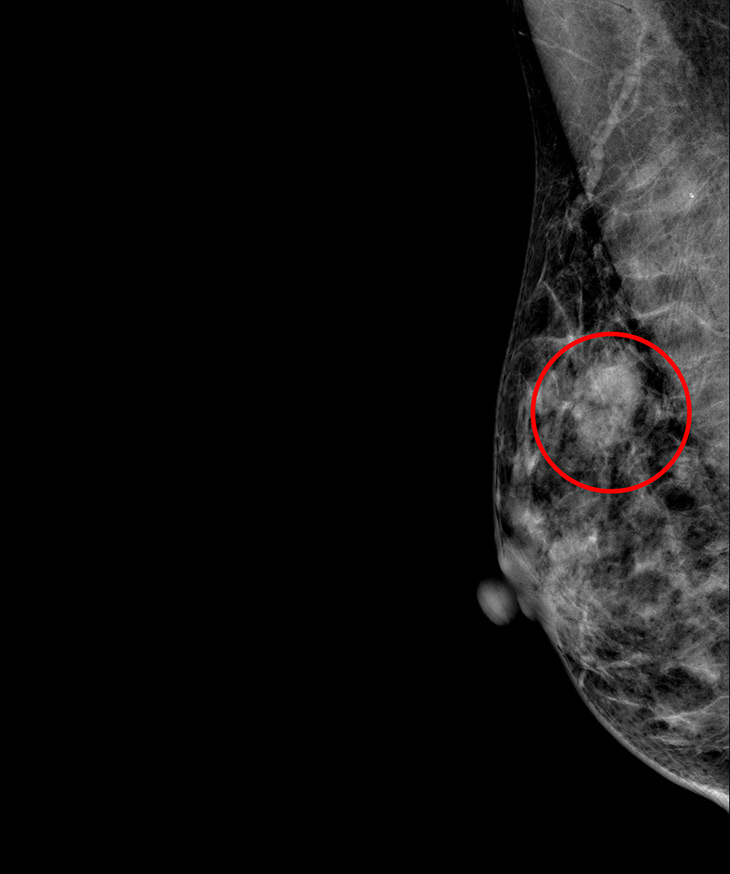

目前新式乳房微創手術有整形式乳房保留手術、內視鏡乳房切除合併重建手術等兩種術式,張群明醫師指出,術後的兩側乳房看起來不會有明顯差別,其中「內視鏡乳房切除合併重建手術」從胸部的側邊接近腋下處打開一個約五公分的傷口,將整個乳房組織取出後,放置義乳重建。適合乳房小、腫瘤小且沒有腋下淋巴結轉移的患者。林小姐身材較嬌小,乳房大小為中等偏小,且腫瘤小於兩公分,因此建議治療方式為內視鏡乳房切除合併重建手術。

乳癌目前依據荷爾蒙受體(雌激素受體,黃體激素受體)與HER2受體,分成三種型態:荷爾蒙受體陽性、HER2受體陽性、三陰性乳癌。林小姐是第一期乳癌,荷爾蒙受體陽性,沒有淋巴結轉移,張群明醫師說,除了為林小姐手術外,再加上口服抗荷爾蒙藥物治療,定期服藥追蹤即可。張群明醫師也提到,現今乳癌治療成績來越來越好,醫療團隊會依照患者的年齡、身體狀況、乳癌不同的受體型態、腫瘤大小、淋巴結有沒有轉移等等,來訂定最適合的治療計畫,目前第一期乳癌五年的平均存活率超過95%;第二期乳癌,平均活率也接近90%;第三期的平均存活率約70%;第四期約25%,只要早期發現,早期治療就有很好的治療結果。